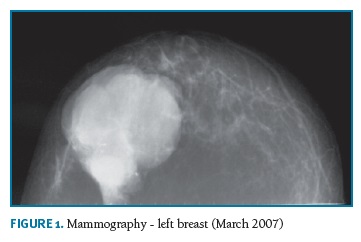

A 74-years-old woman, who has provided her written informed consent, caucasian, menopause at 50 years and was never treated with hormone replacement therapy or contraceptive pills, with past history of myocardial infarction, hypertension and obesity, in March 2007 noticed a tumor in the left breast with 4 cm in largest diameter. At that time, she recurred to Obstetrics and Gynecology Department in Cova da Beira University Hospital Center. Mammographic findings suggested benignity of the lesion (Fig. 1) and a biopsy was performed. Pathologic diagnosis was not definite, suggesting the diagnosis of fibroadenoma or phylloides tumor. The patient refused any further biopsy or surgical treatment. In November 2007, she returned to the same Department with a large 20 cm breast tumor (Fig. 2). A new breast core-biopsy was performed and a pathologic diagnosis of malignancy was excluded. Then, the patient accepted left total mastectomy as the best treatment (Fig. 3).